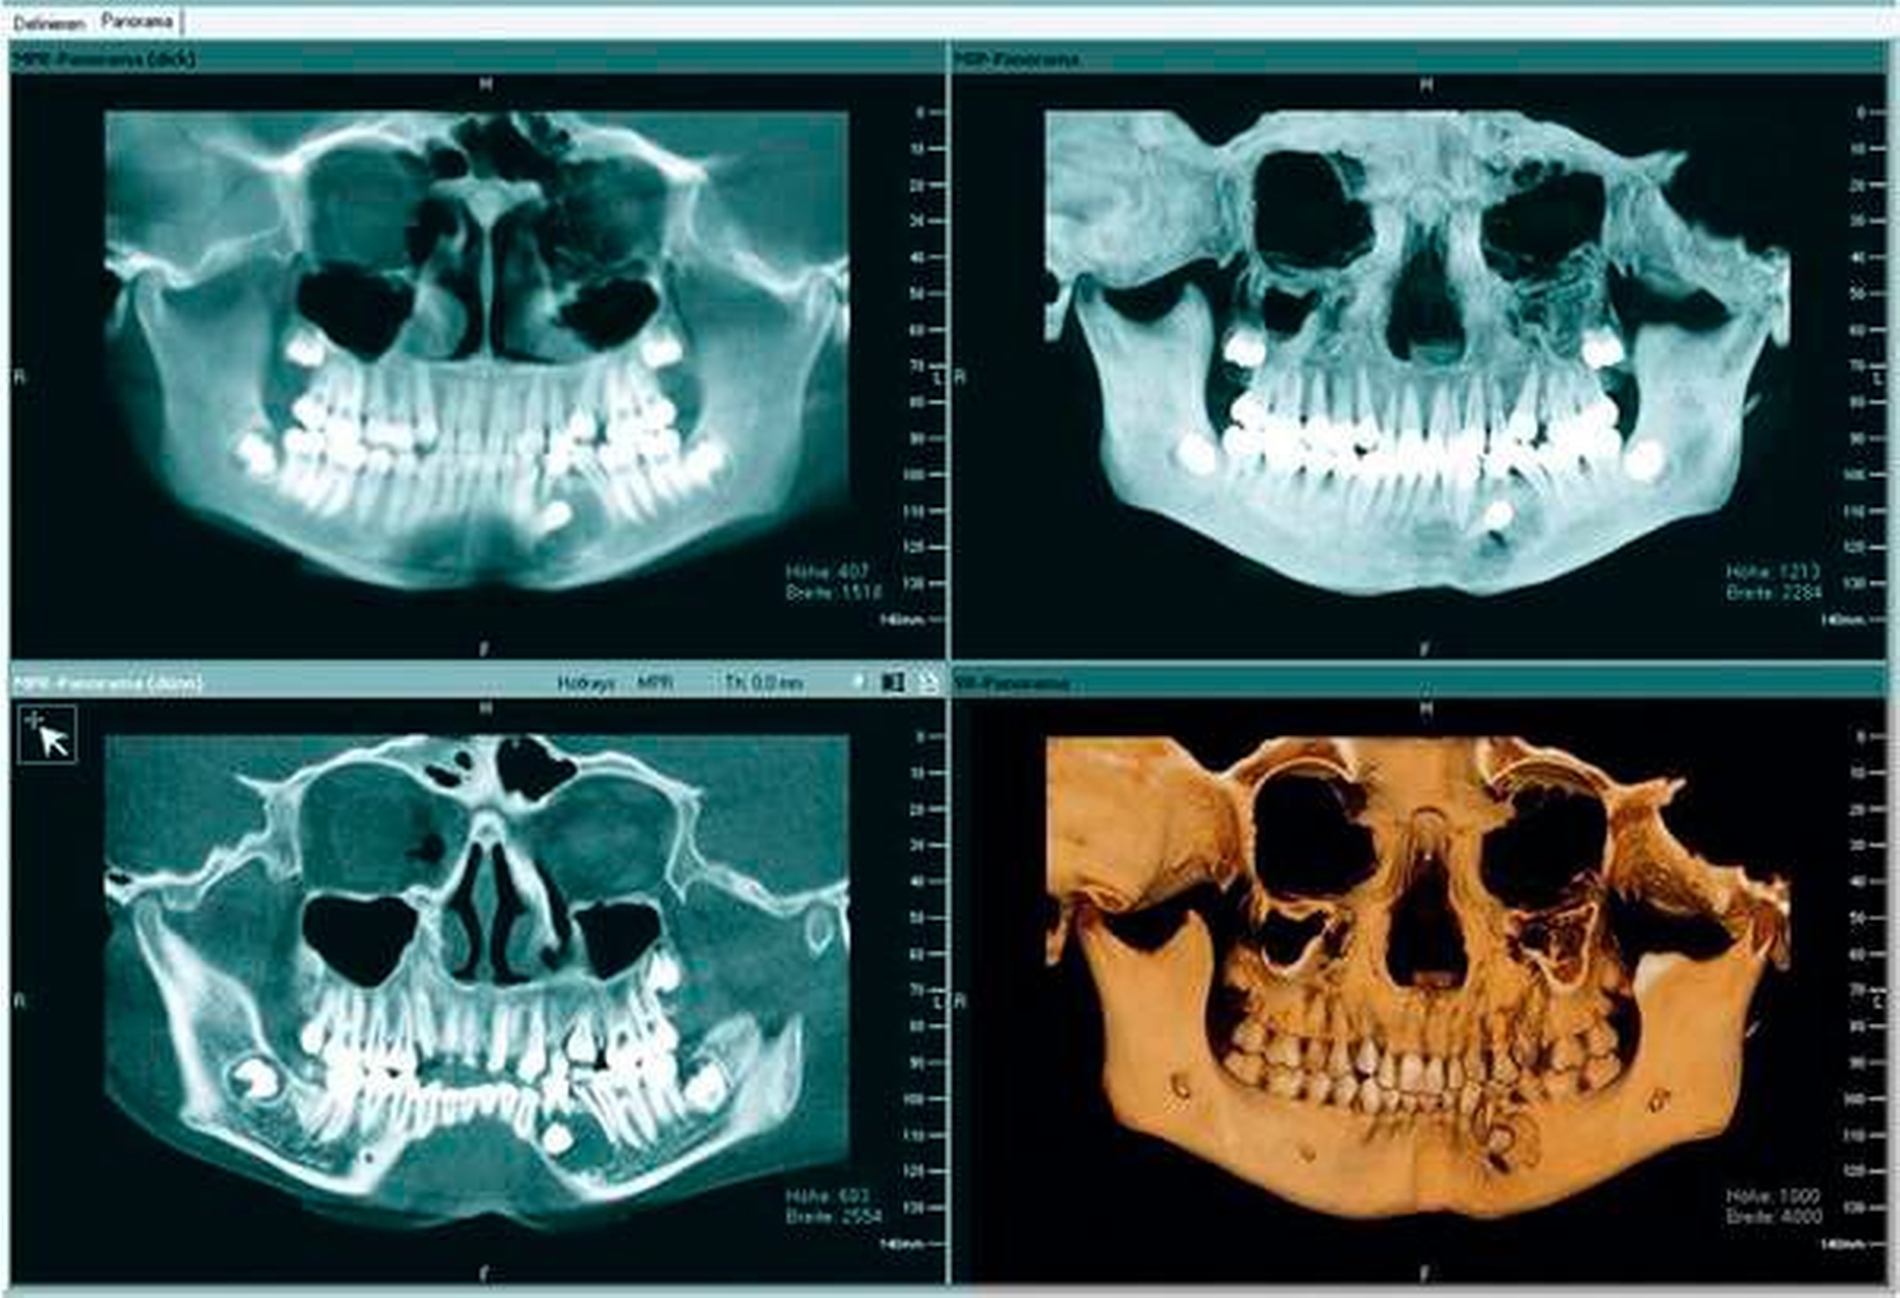

Zur weiteren Therapieplanung wurde ein DVT erstellt, das den persistierenden Zahn 74 zeigte sowie eine große, mutmaßlich follikuläre Zyste, die sich circulär um den Zahn 34 ausdehnt, der seinerseits horizontal verlagert lag und nach schräg distal ausgerichtet war. Der N. alveolaris inferior wurde nach kaudal durch die Raumforderung verdrängt. Die Wurzel lag nach mesial und in der lingualen Kortikalis, die Krone nach vestibulär und distal in das Zystenlumen reichend (Abbildungen 5a bis 5c).

In den regelmäßigen klinischen Kontrollen zeigte sich eine stadiengerechte, reizfreie Wundheilung. Der Zahn 34 konnte mithilfe einer Multibandapparatur sukzessive aus der horizontalen Lage in die Lücke zwischen 33 bis 35 eingeordnet werden und „nahm“ dabei den ihn umgebenden Knochen mit.

In dem Zusammenhang fiel im radiologischen Verlauf vor allem die regrediente Zystenhöhle regio 33 bis 35 auf, die sich im Verlauf von zwei Jahren, sicherlich auch durch die Zahnbewegung durch das Zystenlumen, vollständig konsolidierte.

Die zwischenzeitliche Entfernung der Weisheitszähne diente der Okklusionsstabilisierung und der Prophylaxe eines Engstands (Abbildungen 6 bis 11). Technisch wurden ein Lingualbogen, ein Powerarm zur Elongation und im Verlauf der Behandlung eine feste Apparatur verwendet. An 34 wurde ein Bracket angebracht, ein Supercabble-Bogen als Huckepack-Bogen sowie ein SS-16x22-Trägerbogen eingesetzt.

Im abschließenden OPG war der Zahn 34 regelgerecht eingeordnet, die nach distal deviante Wurzelspitze ist aller Wahrscheinlichkeit nach der Verlagerung geschuldet (Abbildung 8).